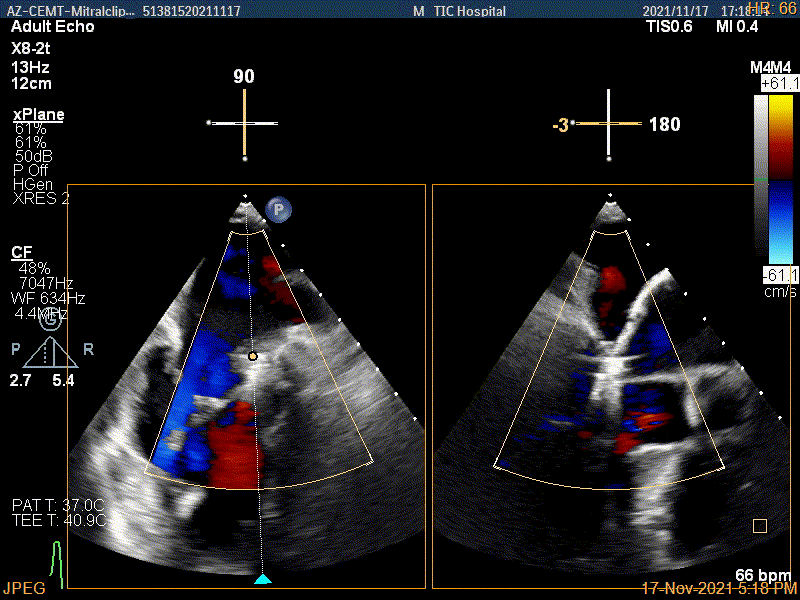

3D证实夹子内侧残余脱垂(P1区)

3Dcolor证实残余分流主要来源于残余脱垂

肺静脉血流频谱逐渐恢复正向,后测量平均跨瓣压差:2mmHg